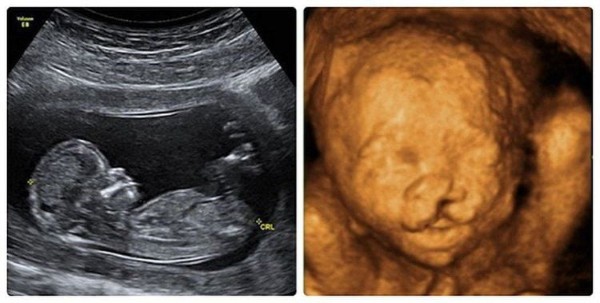

- Siêu âm thai nhi (Ultrasound): Bắt đầu từ tuần thứ 18 đến 22 của thai kỳ, các bác sĩ sản khoa có thể sử dụng siêu âm 3D hoặc 4D để quan sát cấu trúc khuôn mặt của thai nhi.

- Sứt môi: Thường dễ phát hiện hơn qua hình ảnh siêu âm trực diện.

- Hở hàm ếch: Đôi khi khó nhận diện hơn nếu khe hở nằm sâu trong vòm miệng, nhưng các dấu hiệu gián tiếp như lượng nước ối hoặc hình ảnh vòm khẩu cái bất thường sẽ giúp bác sĩ đưa ra nghi vấn.